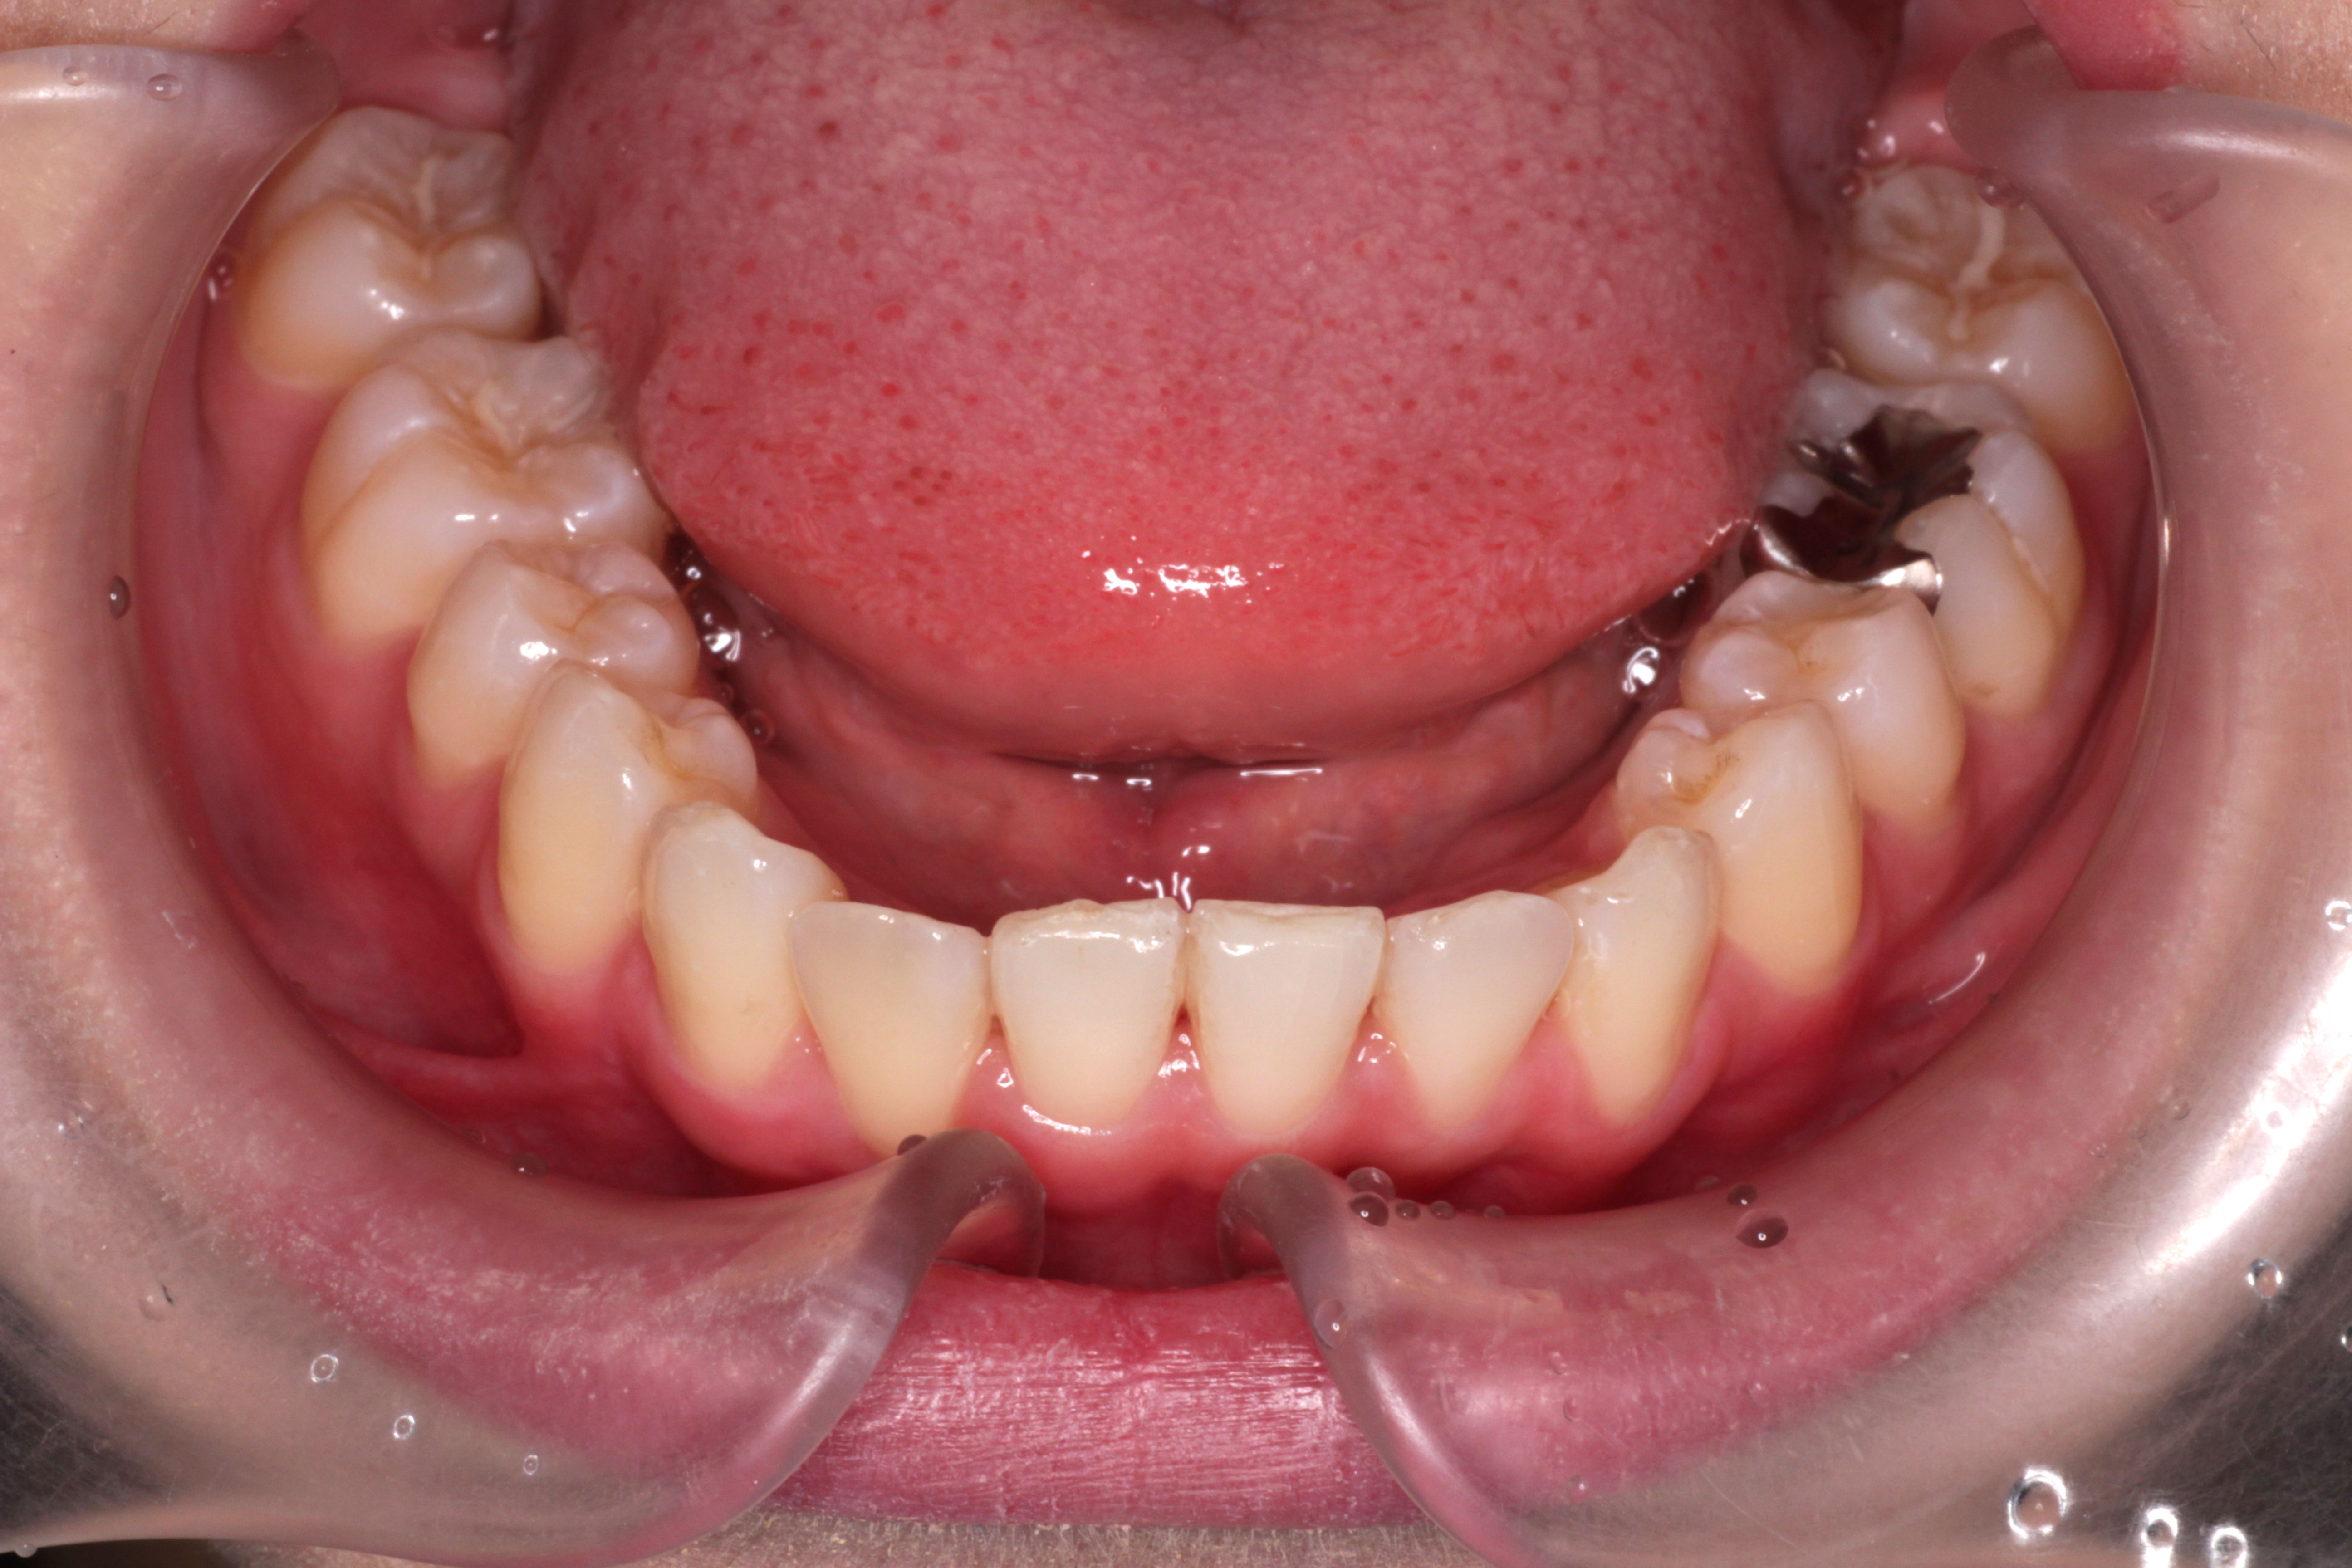

初診時のお口の中の状態です。↓

お口の中の状態としては

⑴咬み合わせが深い。(上の歯がかぶさっていて、下の歯が見えません。)

⑵右下の前から2番目の歯が叢生で歯列に入っていません。

⑶右上の前から2番目の歯が下の歯より前にありません。

診断:上顎前突・前歯部叢生